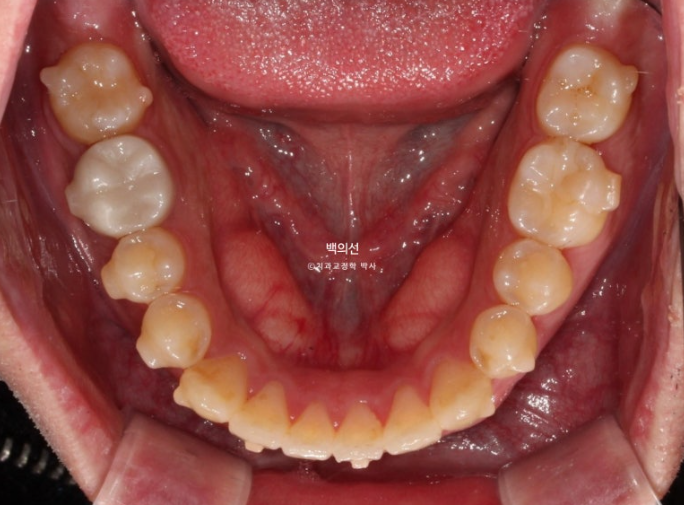

특히 아래 두번째 큰어금니는 쓰러져 있습니다.

노란선이 쓰러져 있는 큰어금니죠. 사랑니를 빼고 세워야 합니다.

문제의 쓰러진 큰어금니는 앞의 큰어금니에 걸려있는 상태로, 인비절라인 투명교정장치 만으로 세우기는 힘들어요.

클리피씨와 같은 브라켓을 붙이고 철사의 힘을 빌려야 합니다.

환자분은 투명교정을 원했기 때문에 투명교정장치 제작 전 쓰러진 어금니와 가위교합을 먼저 개선해놓고, 나머지 앞니 삐뚠 부분은 인비절라인 라이트로 해결하기로 했습니다.

치료시작 3개월차 사진입니다. 먼저 4군데 사랑니를 다 뽑았습니다.

쓰러진 큰어금니와 그 앞의 큰어금니에 총 2개의 브라켓을 붙이고 철사를 넣어 치아를 세웠습니다.

그 사이 입천장에는 가위교합 개선을 위해 교정용 나사 미니스크류를 심고 바깥으로 뻗쳐있던 큰어금니를 제 위치 시켰습니다.